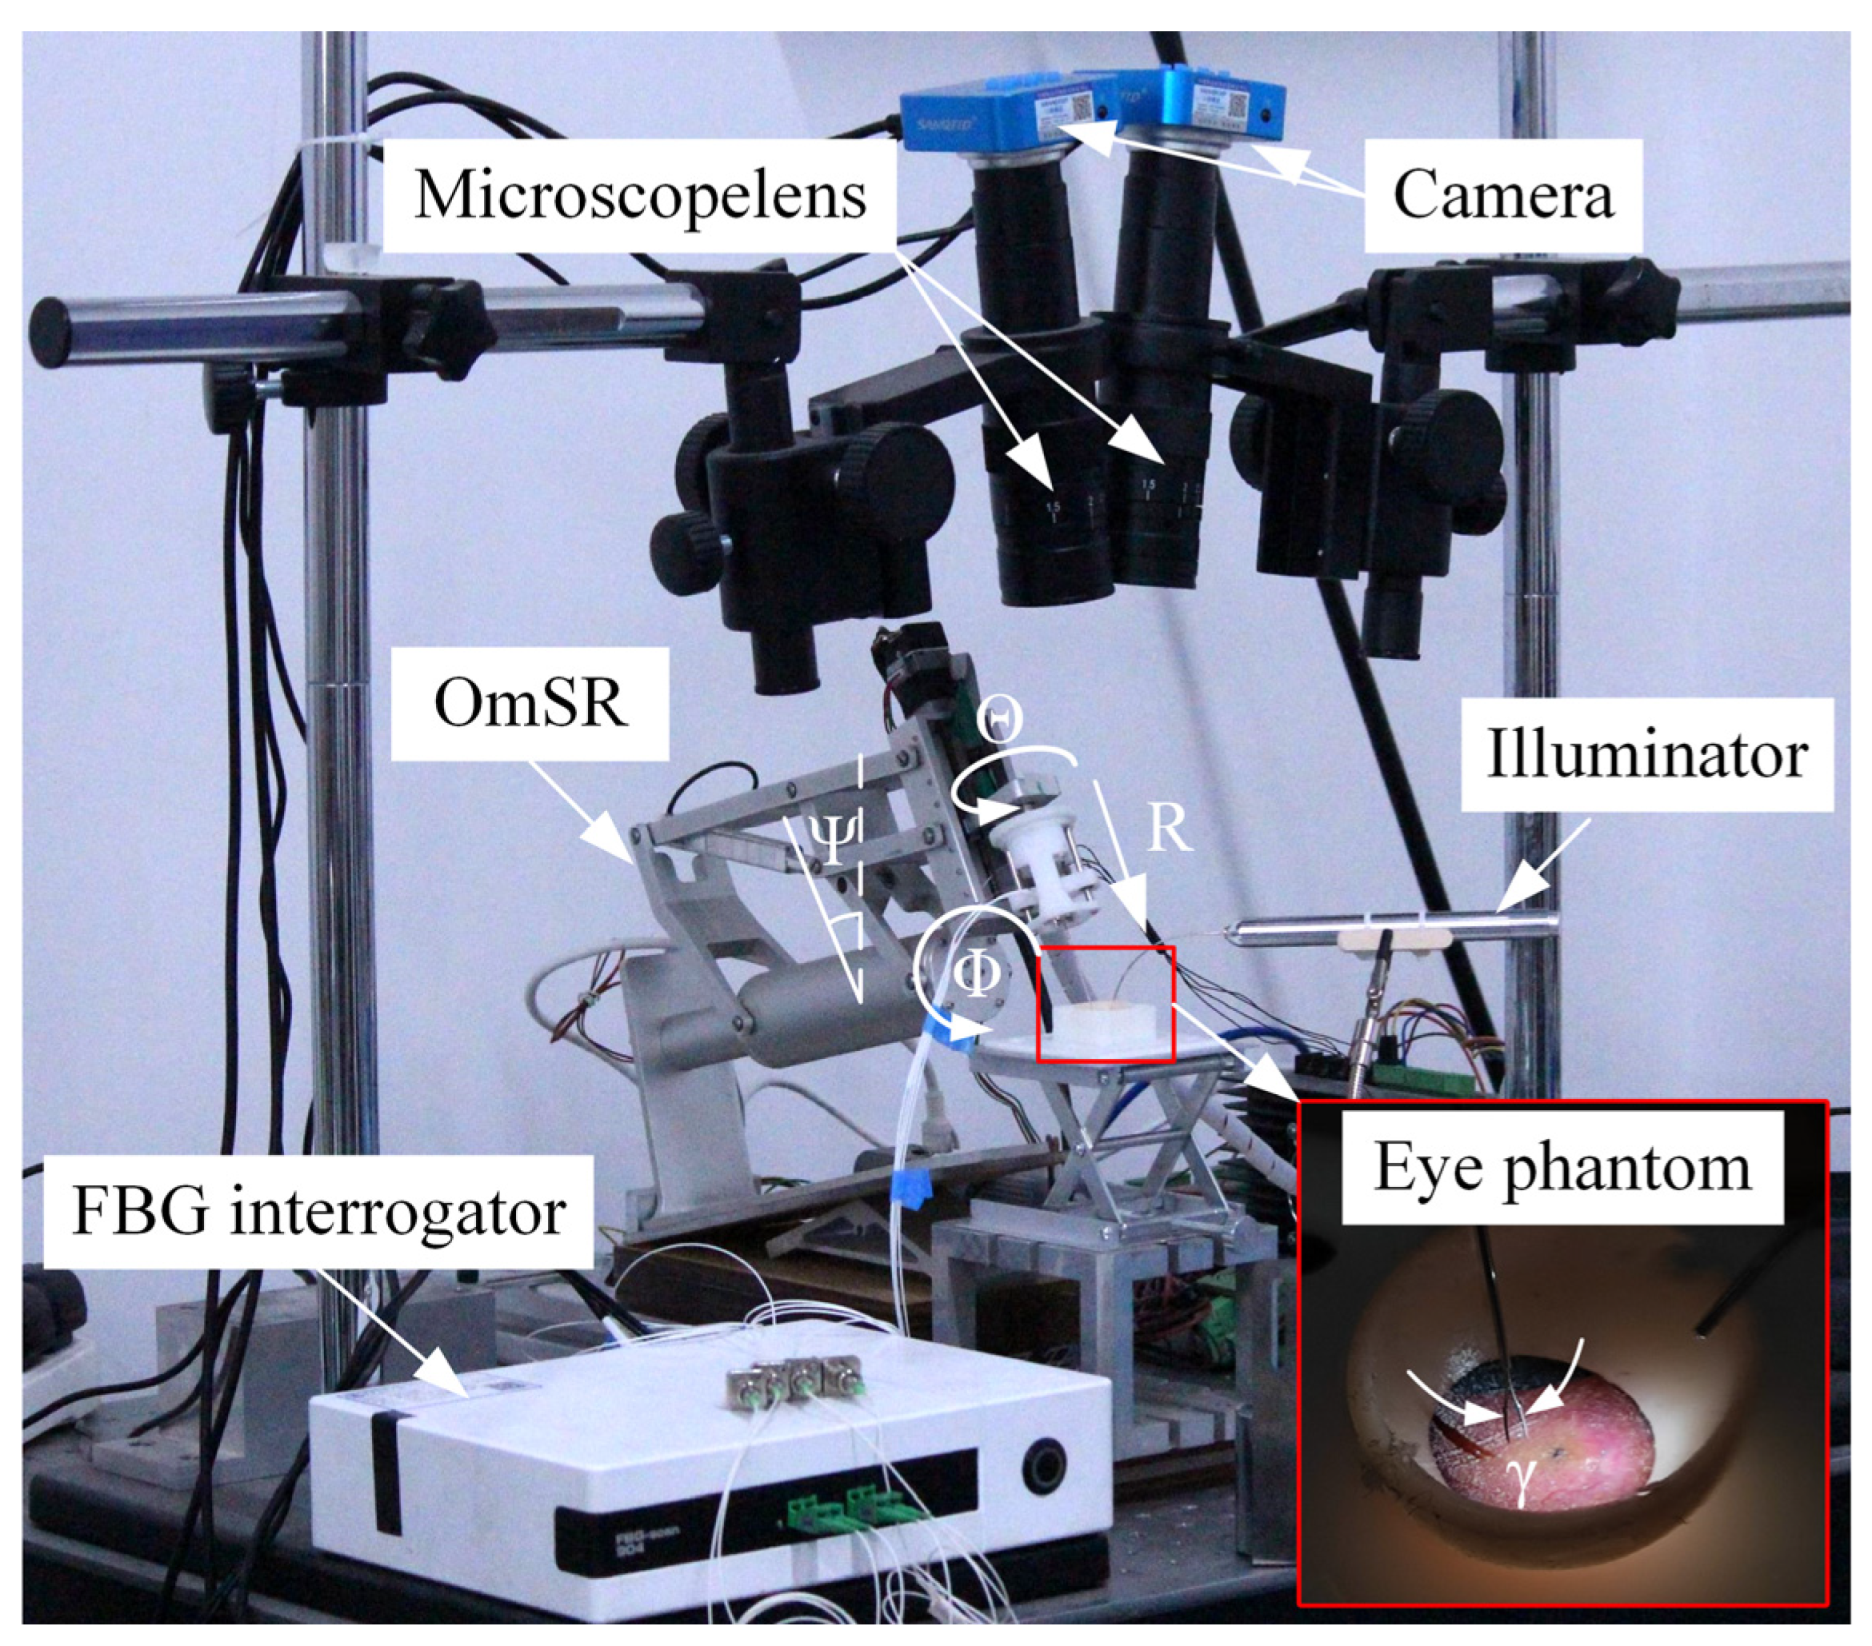

4.1. Experimental Setup